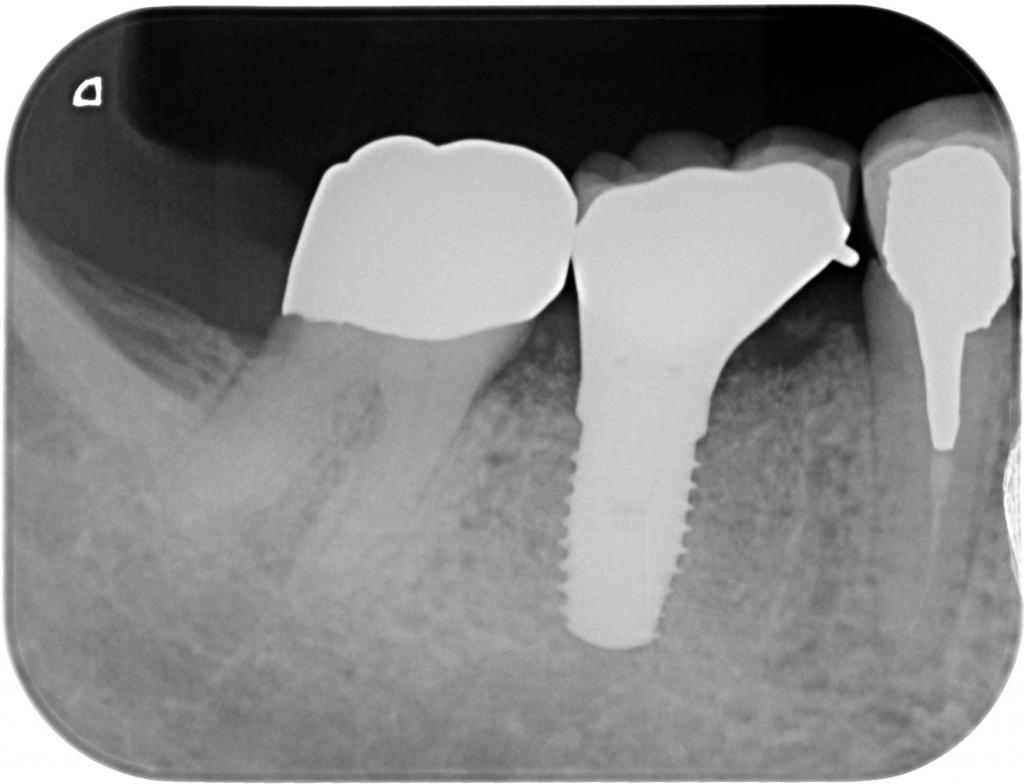

- インプラント埋入後のレントゲン写真です。

適切な位置、方向に埋入されています。